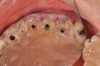

(3. THROUGH 5.) Poly (methyl methacrylate) (PMMA) bridge, custom healing abutment, and view of bridge bonded into place.

Figure 3

Figure 4

Figure 5